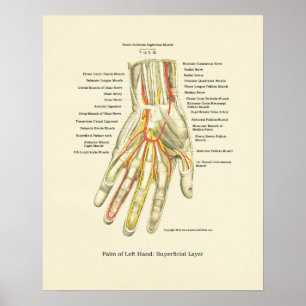

Poster interno da anatomia da mão & do pulso

Preço44,35 €

Poster interno da anatomia da mão & do pulso

Preço48,95 €

Poster interno da anatomia da mão & do pulso

Preço44,35 €

Poster interno da anatomia da mão & do pulso

Preço48,95 €

Poster interno da anatomia da mão & do pulso

Preço48,95 €

Poster de Anatomia Interna da Mão e Pulso

Preço44,35 €